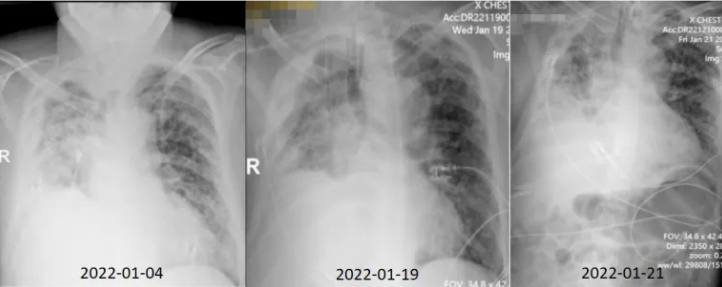

床旁胸片:入院初,患者双肺渗出较多,右肺为著。经过一段时间的治疗,肺内病灶逐渐得到控制(图10)。

图10 患者治疗过程中胸片变化

2022年1月28日复查胸部CT:双肺感染仍然较重,虽未完全吸收,但较前有好转(图11)。

图11 复查胸部CT(2022-01-28)